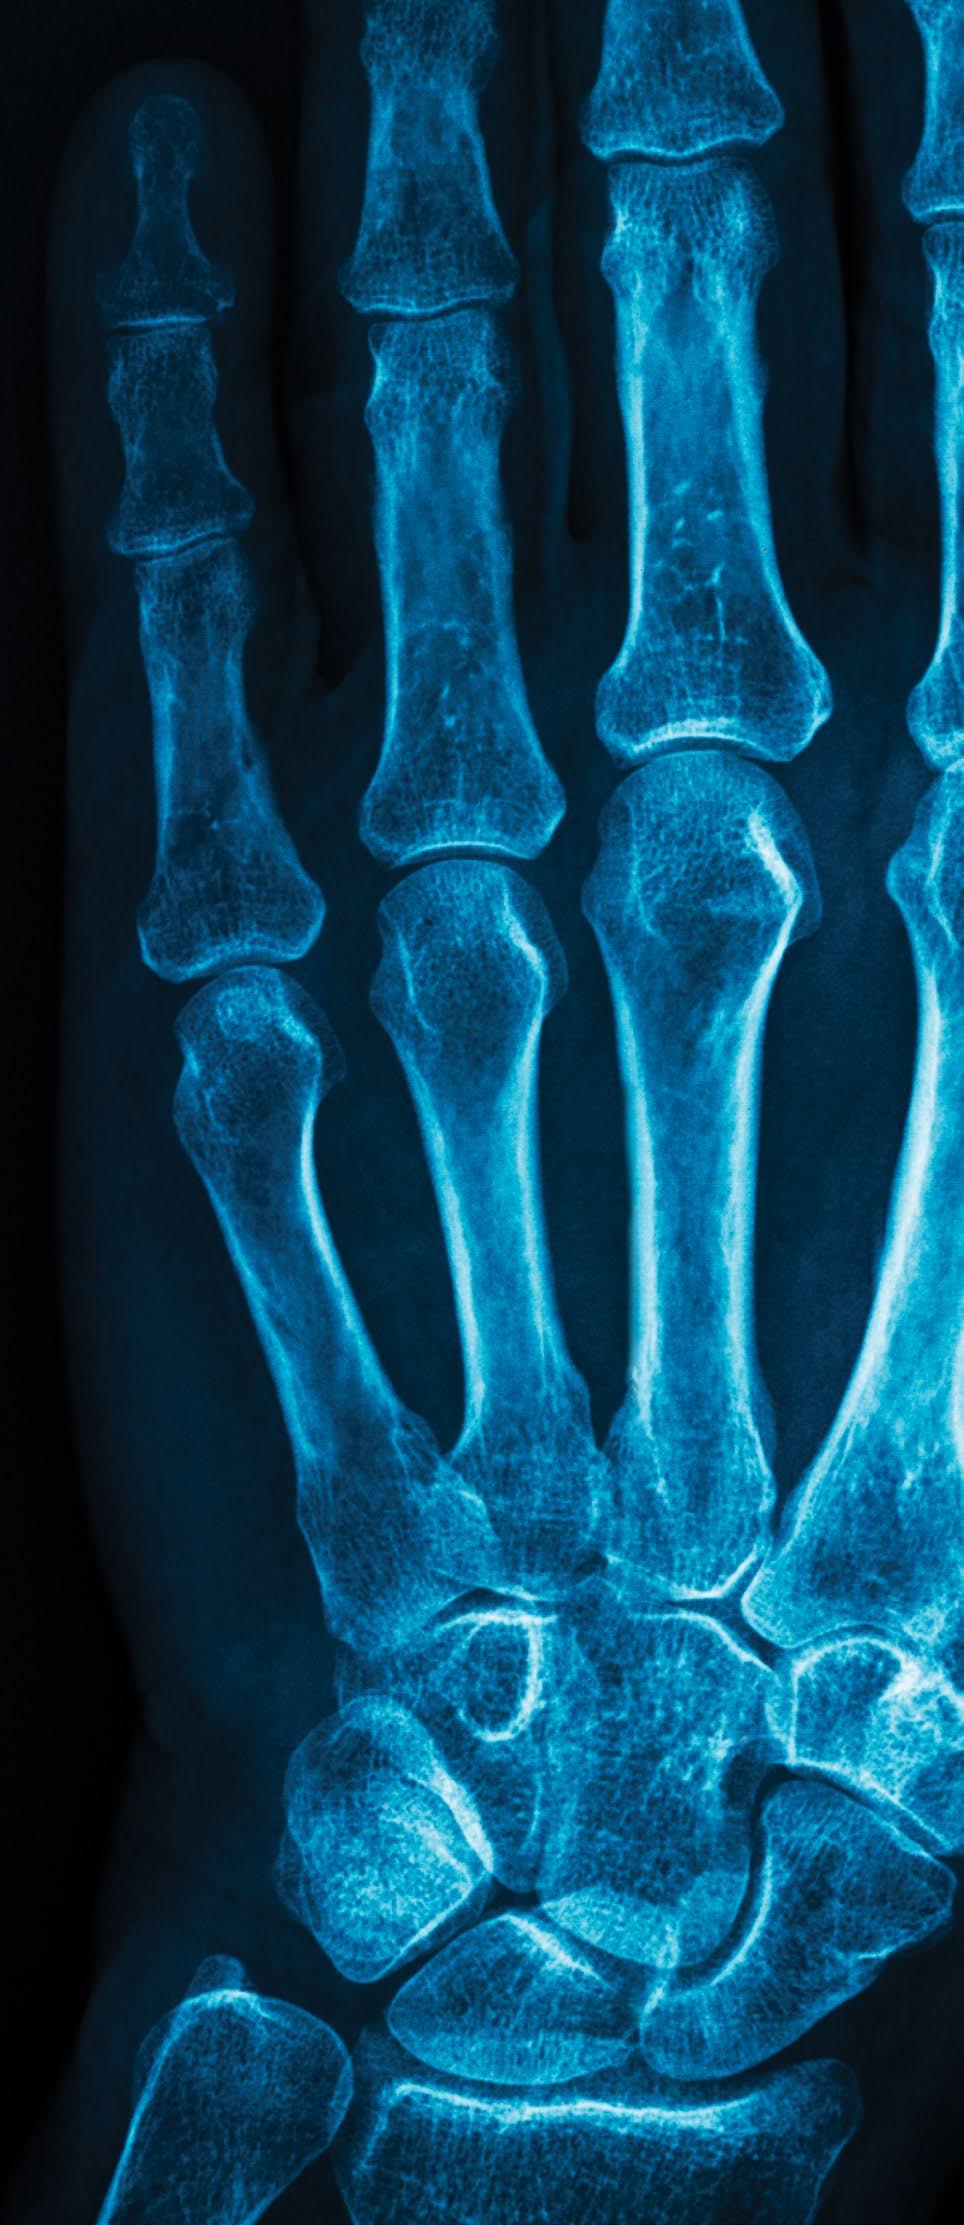

1895 X-rays

Physicist Wilhelm Röntgen discovers that X-rays could show bones inside the human body. Röntgen received the first Nobel Prize in Physics in 1901 for his discovery, which sparked the use of X-rays in medical practice and inspired further research into these ‘remarkable rays’ [7] .

X-rays are familiar to anyone who has ever broken a bone as they allow us to ‘see’ organs inside the body, especially those made of dense tissue, such as bone. CT scans (computerised tomography) use X-rays to gather data in computer-simulated slices through the body. The images produced by CT scans allow 3D imaging whereas standard X-rays are 2D. These scans can be used for better targeting of radiation treatment for cancers. In 2018, a team of scientists at the University of Canterbury, New Zealand, developed a special type of 3D X-ray scanner to differentiate various materials or tissues, providing more diagnostic information than standard CT [35] .